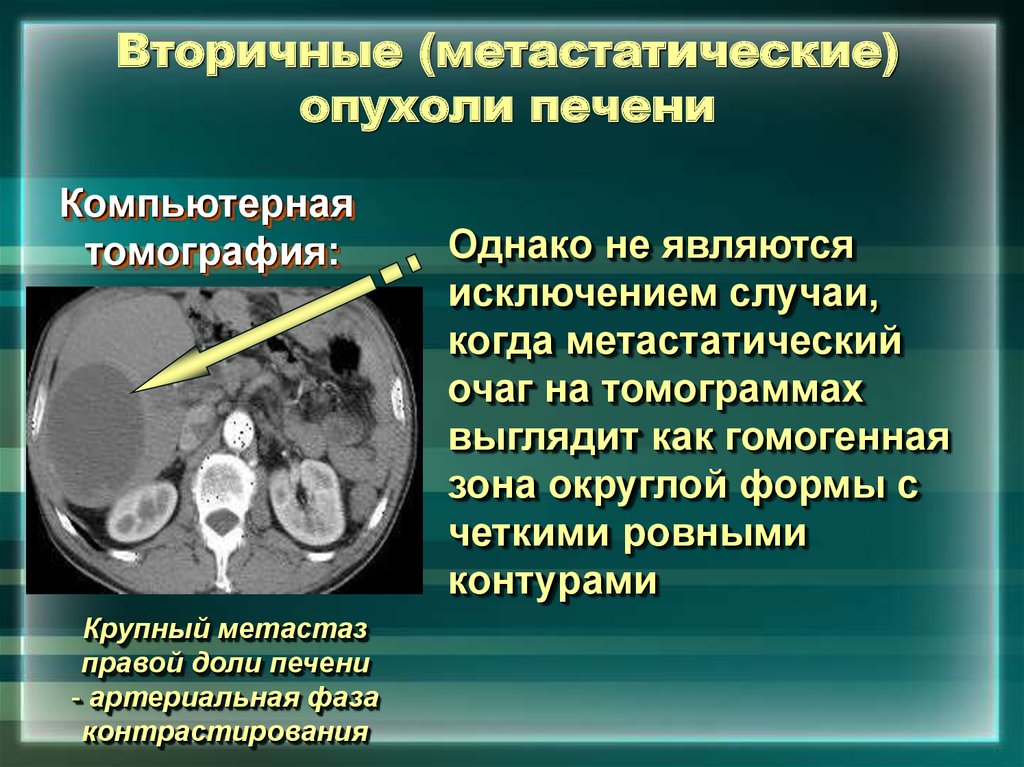

Метастатические поражения печени в ультразвуковом изображении характеризуются